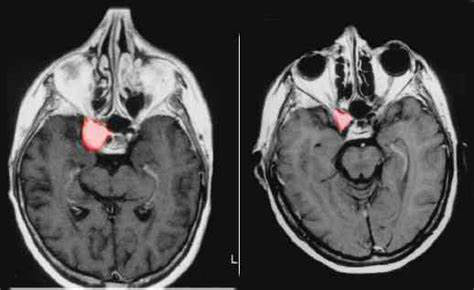

海绵窦脑膜瘤——良性但具有威胁性的肿瘤——位于难以进入的位置。它们位于大脑底部的头骨上方,被至少五条脑神经和颈内动脉包围。在不损害对功能至关重要的显微解剖结构的情况下治疗这些肿瘤是神经外科医生面临的较大挑战之一。

由于意识到手术切除整个肿瘤而不造成附带损害是不可行的,脑瘤专家通过用精确靶向立体定向放射外科手术治疗这些肿瘤来作出反应。这种策略对位于海绵窦内的较小肿瘤很合适,但当应用于边界超出海绵窦并导致视神经受压的大肿瘤时,这种治疗可能会引起并发症。

处理大型海绵窦脑膜瘤的较佳方法包括手术和放射外科手术。首先,进行海绵窦减压手术。打开这个解剖区域,在这个“顺利”的区域移除(去除)全部的肿瘤组织。这释放了脑神经,使其功能得以恢复。它还允许对海绵窦内的肿瘤进行更顺利的放射治疗。